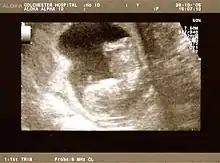

The result of an ultrasonography: a black and white image that shows a clear view of the interior abdomen

Obstetric ultrasonography is routinely used for dating the gestational age of a pregnancy from the size of the fetus, determine the number of fetuses and placentae, evaluate for an ectopic pregnancy and first trimester bleeding, the most accurate dating being in first trimester before the growth of the foetus has been significantly influenced by other factors.[22] Ultrasound is also used for detecting congenital anomalies (or other foetal anomalies) and determining the biophysical profiles (BPP), which are generally easier to detect in the second trimester when the foetal structures are larger and more developed.[23]

X-rays and computerized tomography (CT) are not used, especially in the first trimester, due to the ionizing radiation, which has teratogenic effects on the foetus.[24] No effects of magnetic resonance imaging (MRI) on the foetus have been demonstrated,[25] but this technique is too expensive for routine observation. Instead, obstetric ultrasonography is the imaging method of choice in the first trimester and throughout the pregnancy, because it emits no radiation, is portable, and allows for realtime imaging.[26]

The safety of frequent ultrasound scanning has not been confirmed. Despite this, increasing numbers of women are choosing to have additional scans for no medical purpose, such as gender scans, 3D and 4D scans.[27] A normal gestation would reveal a gestational sac, yolk sac, and fetal pole.[28]

The gestational age can be assessed by evaluating the mean gestational sac diameter (MGD) before week 6, and the crown-rump length after week 6. Multiple gestation is evaluated by the number of placentae and amniotic sacs present.[29]